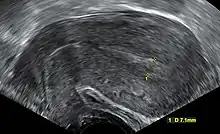

| An ultrasound showing a gestational sac containing a yolk sac but no embryo | |